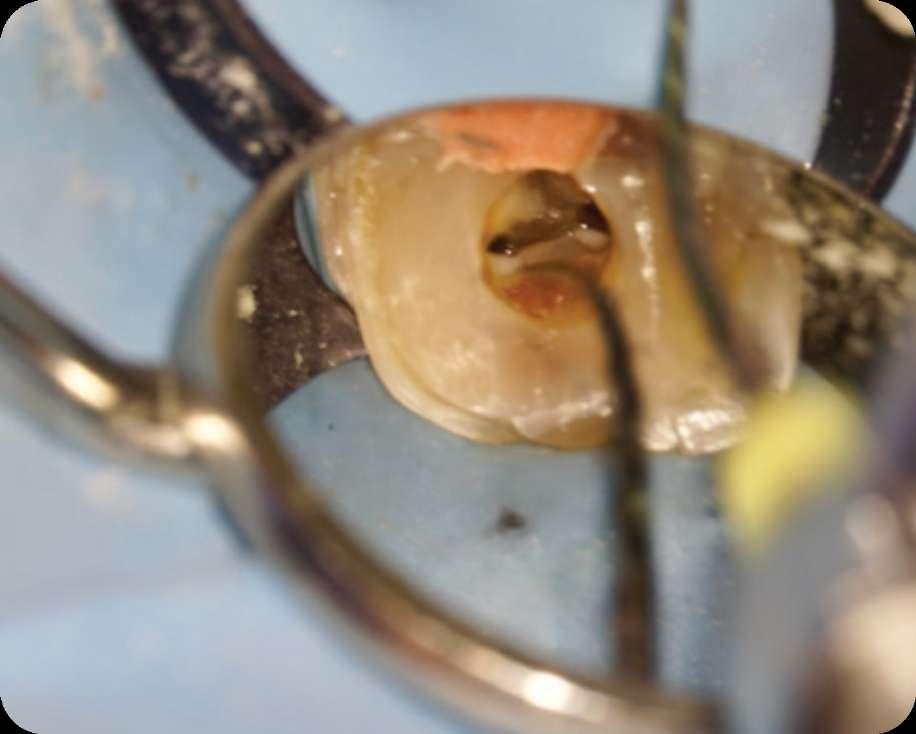

Die Revisionsbehandlung erfolgte in zwei Sitzungen. Nach Anlegen des Kofferdams wurde die provisorische Füllung entfernt und die Zugangskavität gereinigt. Im Anschluss erfolgte die intrakoronale Diagnostik (Abbildung 11). Es zeigte sich bakteriell besiedeltes Wurzelfüllmaterial im mesiobukkalen, distobukkalen und palatinalen Kanal. Das Orifizium des mesiobukkalen Kanals war in palatinaler Richtung erweitert. Die Entfernung eines mesialen Dentinüberhangs mit langschaftigen Rosenbohrern legte das weit nach palatinal verlagerte Orifizium des zweiten mesiobukkalen Kanals frei. Die Entfernung des Wurzelfüllmaterials erfolgte mithilfe von EdgeFile X7 der Größe 25.06, und 17.06 in Crown Down Technik um die Verschleppung von Keimen und bakteriell besiedeltem Wurzelfüllmaterial nach apikal zu reduzieren. Die Erschließung und initiale Aufbereitung des zweiten mesiobukkalen Kanals wurde mithilfe der EdgeFile X7 der Größe 17.04, 17.06 in alternierender Weise wie oben beschrieben durchgeführt. Nach elektrometrischer Bestimmung der Arbeitslänge aller Kanäle wurde die Präparation mit EdgeFile X7 auf voller Arbeitslänge fortgesetzt. Im ersten mesiobukkalen Kanal, distobukkal und palatinal wurde die Aufbereitung mit EdgeFile X7 der Größe 40.06 abgeschlossen, während der zweite mesiobukkal Kanal bis 30.06 aufbereitet wurde (Abbildung 13).

Abbildung 11: Nach Ausarbeiten der primären Zugangskavität; Darstellung des mb2 in der Nähe des palatinalen Kanals